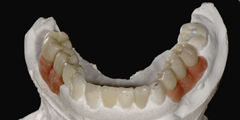

診断用ワックスアップ作成

咬合器付着後に模型上で理想的な咬合関係の構築モデルを作製する事。

技工士-歯科医師-患者様の三者間での具体的ゴールの設定と状況に応じた複数の治療プランの提示可能。